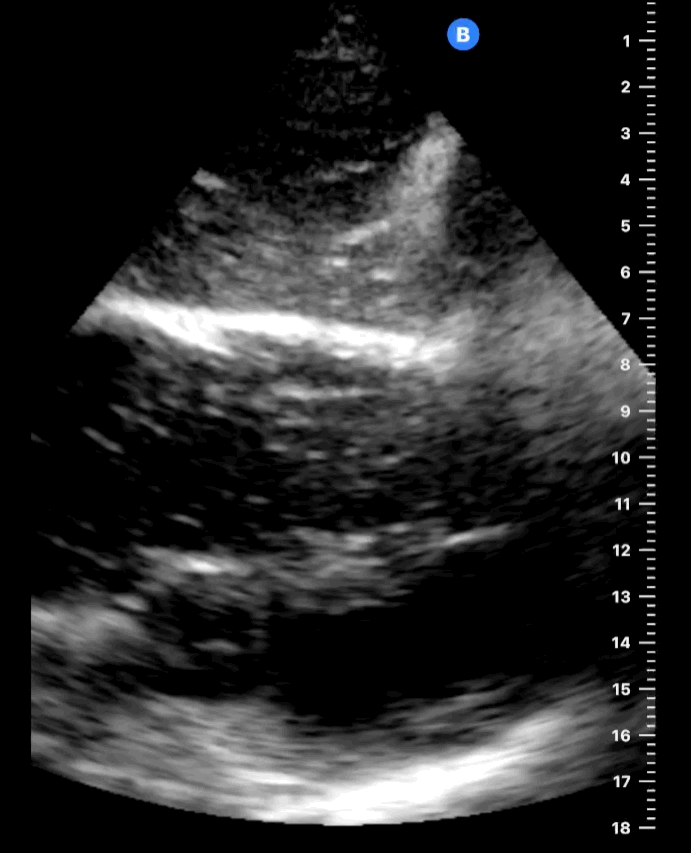

PLAX view

This PLAX view shows cardiac standstill, with no activity seen in the heart musculature or valves. The slight movement visible in the clip is due to patient ventilation, not cardiac activity. Small air bubbles are seen circulating within the right ventricle, confirming that there is no blood flow through the heart, further indicating the absence of effective cardiac output during the arrest.